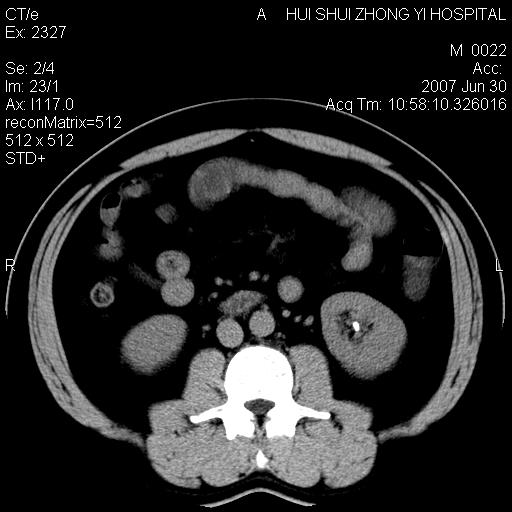

男,44岁,体检。

双肾结石

双侧肾盂、输尿管内结石,双侧肾脏轮廓呈波浪状,可能以前有过感染的

支持双肾结石,肝右叶低密度影为胆囊部分容积效应。

肝右叶低密度影为胆囊部分容积效应?为什么s43.0层面下来不见胆囊影,而是相隔了一层才见胆囊影。这是按我们扫描的顺序发的,但是是追加扫描的。

病人呼吸动了,第四层应该在第五\\六层之间。肝右叶低密度影为胆囊部分容积效应。双肾结石。

双肾结石,少量腹腔水?